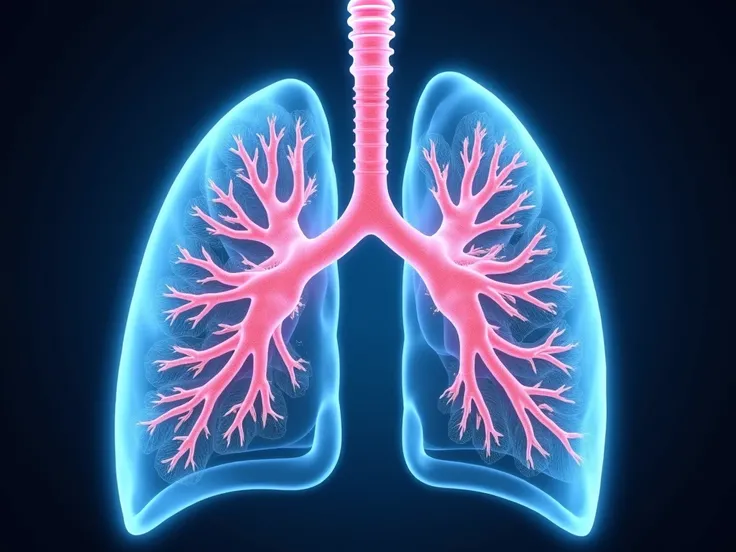

Make a folder about bacterial pneumonia

Make a folder about bacterial pneumonia